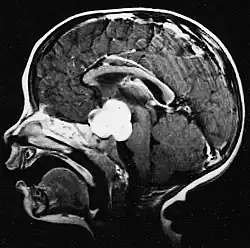

Cette tumeur est typique de la fosse postérieure, où elle est localisée dans les deux hémisphères du cervelet ou dans le vermis cérébelleux. Parce qu'il est envahissant et à croissance rapide, il se propage généralement à d'autres parties du système nerveux central (SNC) via le LCR et peut infiltrer le plancher du quatrième ventricule voisin et les méninges. Plus rarement, des métastases supplémentaires du SNC peuvent survenir. Lorsque la tumeur maligne survient, les symptômes comprennent la perte d'équilibre, l'incoordination, la diplopie, la dysarthrie et l'atteinte du quatrième ventricule, ce qui entraîne souvent une hydrocéphalie obstructive, des maux de tête, des nausées et des vomissements et une démarche instable.

L'IRM montre généralement une lésion de contraste massive impliquant le cervelet. Comme mentionné ci-dessus, le médulloblastome a une forte propension à infiltrer localement les leptoméninges ainsi qu'à se propager à travers l'espace sous-arachnoïdien, impliquant les ventricules, la convexité cérébrale et les surfaces leptoméningées de la colonne vertébrale. Par conséquent, il est nécessaire de mettre en résonance tout l'axe crânio-spinal.